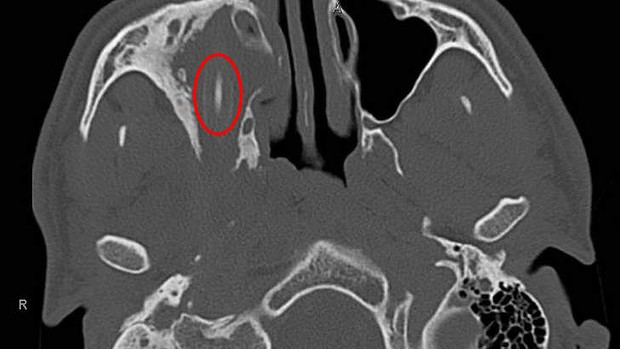

Μια εξέταση απέδειξε ότι μέσα στο κεφάλι του υπήρχε ένα μολύβι 10 εκατοστών. Οι γιατροί το αφαίρεσαν και ο ασθενής ήταν μια χαρά στην υγεία του.